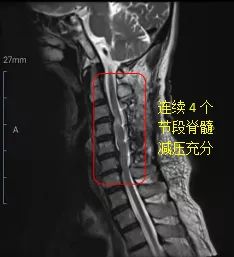

针对这样的特殊病例,脊柱专业组组长吴晓荣主任医师立即组织了科室的病例讨论,脊柱专业组成员对病例进行了深入的分析和讨论,最终决定采用“颈椎单开门技术”对颈脊髓进行长节段的充分减压,并做了详细的手术计划及术中预案。2个小时的手术过程非常顺利,术中采用稳定的Mayfield头架固定体位,进口磨钻动力系统完成“开门”,固定则采用了当下先进的centerpiece钉板系统。麻醉清醒后患者直接回到普通病房予以监护,术后第2天佩戴颈托开始下地活动,患者的四肢麻木感逐渐缓解,双手力量逐渐恢复。出院前,患者已能拿持物品,已恢复部分生活自理能力,并会在后续的治疗中得到持续的改善。患者术后的颈椎磁共振检查也可以看出受压的脊髓都得到了充分的减压(图2),患者及家属都对治疗效果十分满意。

图2.术后复查颈椎磁共振